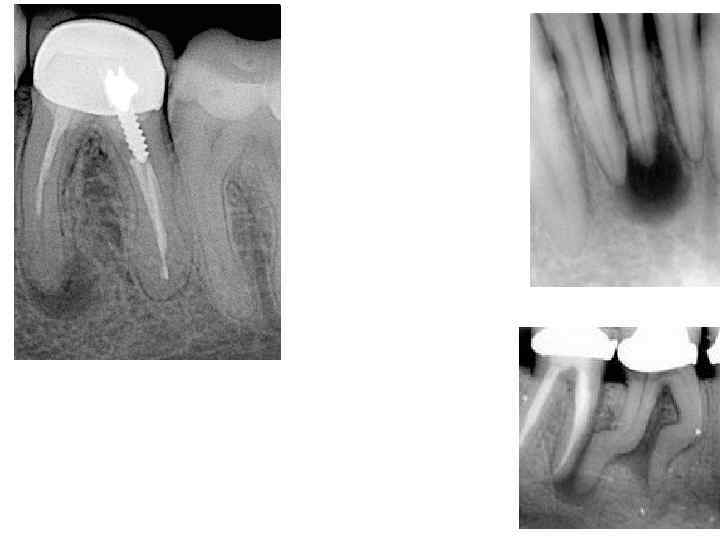

Диагностика хронического периодонтита • основывается на клинической картине и рентгенологических данных. На рентгенограмме при гранулирующем периодонтите обнаруживаются типичные изменения — очаг разрежения костной ткани в области верхушки корня. Линия периодонта в этом отделе не видна из -за инфильтрирующего роста грануляционной ткани, приводящего к рассасыванию стенок лунки, а также цемента и дентина корня. Поверхности их становятся неровными. Эту неровность выявляют более отчетливо со стороны костной ткани, в которую из периодонта идут небольшие выросты

Диагностика • основывается на клинической картине, но чаще всего на рентгенологических данных. На рентгенограмме при гранулематозном периодонтите в околоверхушечной области виден округлый очаг разрежения костной ткани с четкими ровными границами. При правильно проведенном консервативном лечении на месте гранулематозного очага выявляют изменения, характерные для фиброзного периодонтита, или образование участка склерозированной костной ткани

Диагностика • основывается на данных рентгенографии. На рентгенограмме выявляют расширение линии периодонта, главным образом у верхушки корня зуба. Иногда в результате гиперцементоза обнаруживают значительное утолщение верхушечного участка корня. Костная пластинка, ограничивающая расширенную линию периодонта, нередко утолщена, склерозирована